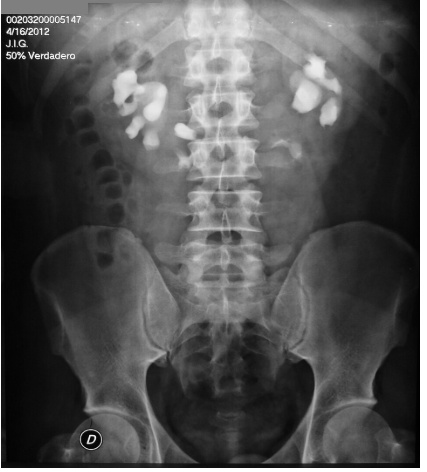

- Imagem Pós-Miccional: Crucial para avaliar o resíduo e o esvaziamento completo dos ureteres.

- Pós-miccional: Esvaziamento quase completo.

5.3. Obstruções:

Dilatação progressiva do sistema coletor. A UIV é excelente para mostrar o nível e a causa da obstrução.